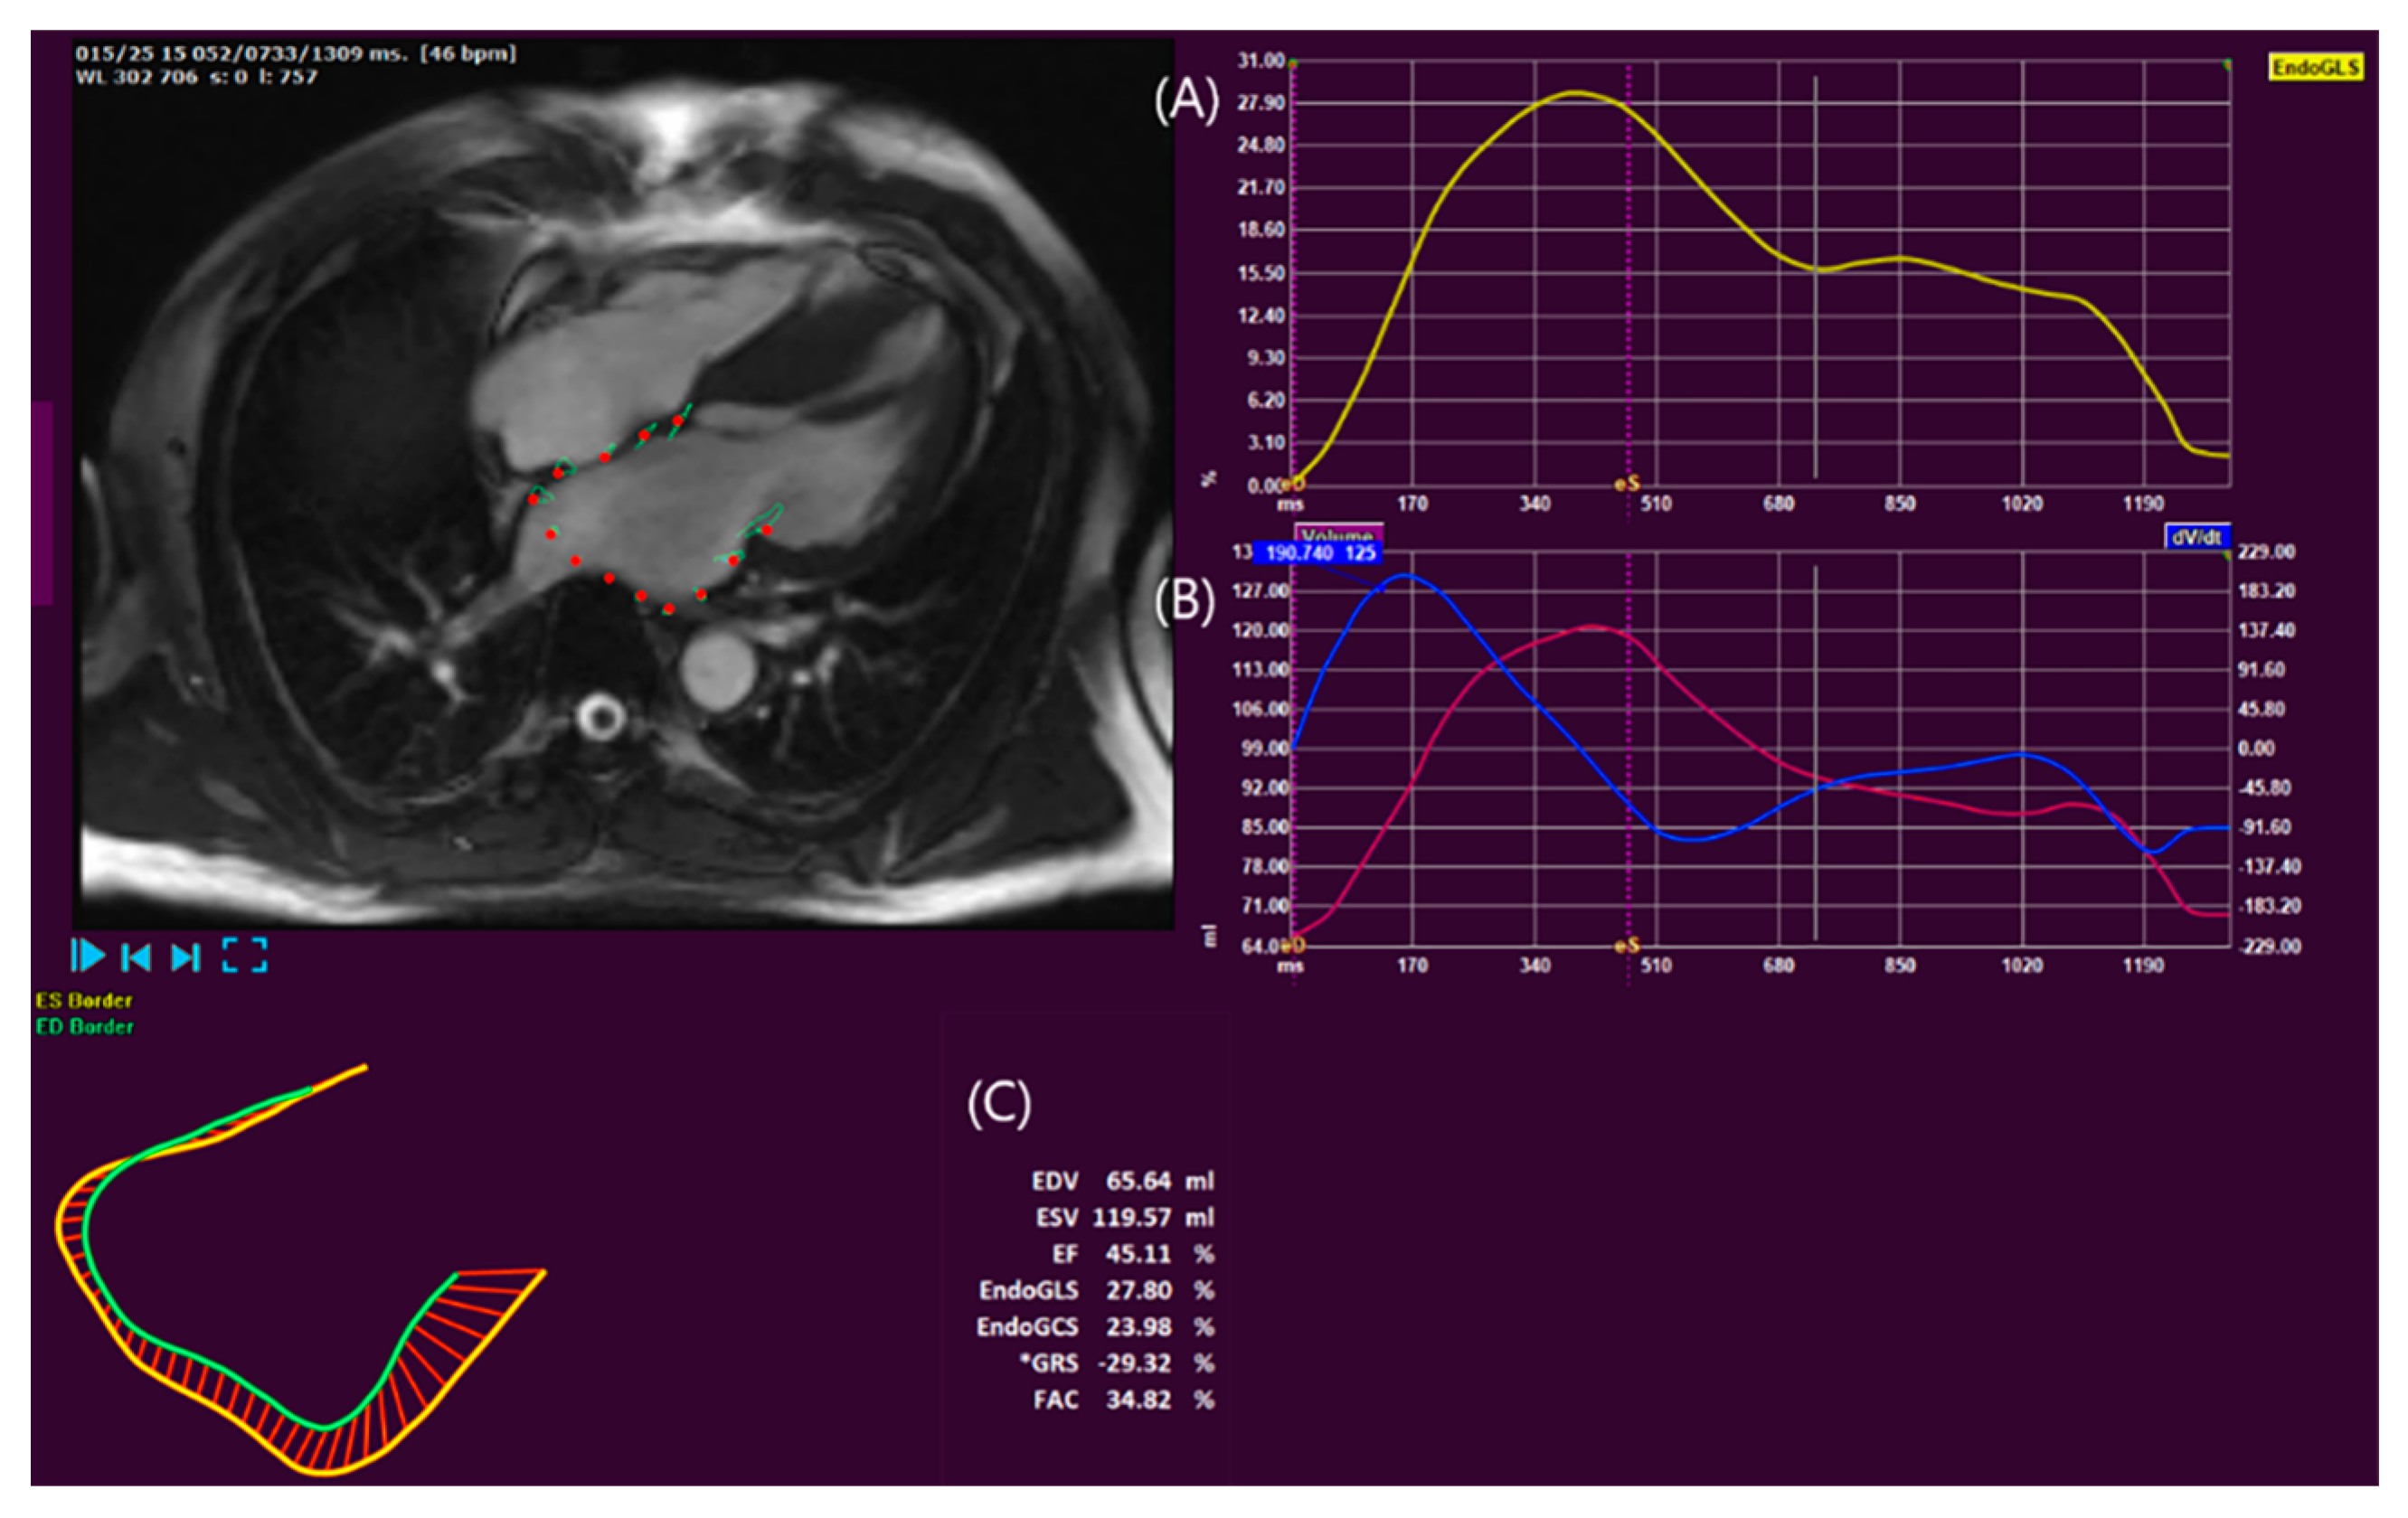

- Cau, R.; Bassareo, P.; Suri, J.S.; Pontone, G.; Saba, L. The emerging role of atrial strain assessed by cardiac MRI in different cardiovascular settings: An up-to-date review. Eur. Radiol. 2022, 32, 4384–4394. [Google Scholar] [CrossRef]

- Truong, V.T.; Palmer, C.; Wolking, S.; Sheets, B.; Young, M.; Ngo, T.N.M.; Taylor, M.; Nagueh, S.F.; Zareba, K.M.; Raman, S.; et al. Normal left atrial strain and strain rate using cardiac magnetic resonance feature tracking in healthy volunteers. Eur. Heart J. Cardiovasc. Imaging 2020, 21, 446–453. [Google Scholar] [CrossRef]

- Bertelsen, L.; Diederichsen, S.Z.; Haugan, K.J.; Brandes, A.; Graff, C.; Krieger, D.; Kronborg, C.; Køber, L.; Højberg, S.; Vejlstrup, N.; et al. Left atrial volume and function assessed by cardiac magnetic resonance imaging are markers of subclinical atrial fibrillation as detected by continuous monitoring. Europace 2020, 22, 724–731. [Google Scholar] [CrossRef]

- Yang, Y.; Yin, G.; Jiang, Y.; Song, L.; Zhao, S.; Lu, M. Quantification of left atrial function in patients with non-obstructive hypertrophic cardiomyopathy by cardiovascular magnetic resonance feature tracking imaging: A feasibility and reproducibility study. J. Cardiovasc. Magn. Reson. Off. J. Soc. Cardiovasc. Magn. Reson. 2020, 22, 1–11. [Google Scholar] [CrossRef]